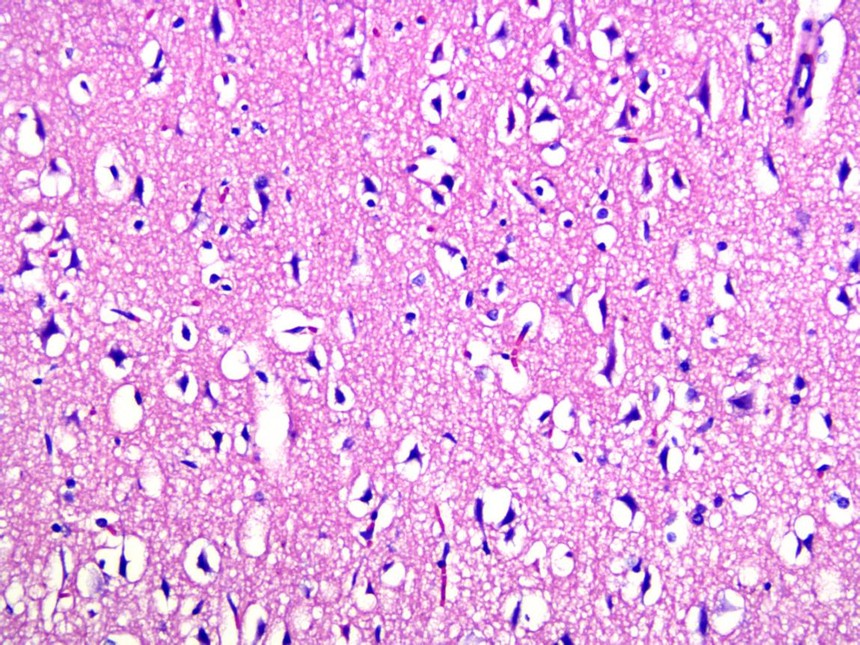

对脑组织进行病理分析,模型组得大脑皮层有明显得神经元损伤,排列不规则,水肿严重

正常 击打模型

对脑组织神经元进行尼氏染色,模型组尼氏小体数量明显减少,神经元排列紊乱